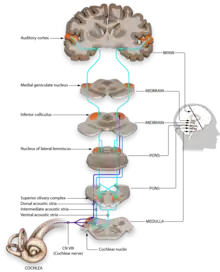

(Central) Auditory Perception Disorder (APD) (også kaldet CAPD) er samlebetegnelsen for tilstande, hvor hjernen har svært ved at bearbejde høreindtryk, selvom hørelsen som sådan fungerer normalt.[1][2][3] Patienter med APD har således et normalt lydinput fra det indre øre og videre til hørenerven, men centralnervesystemet har problemer med at opfatte og bearbejde lydindtrykket i de centrale hørebaner, der inkluderer hørecenteret, som ligger i hjernebarkens tindingelap.